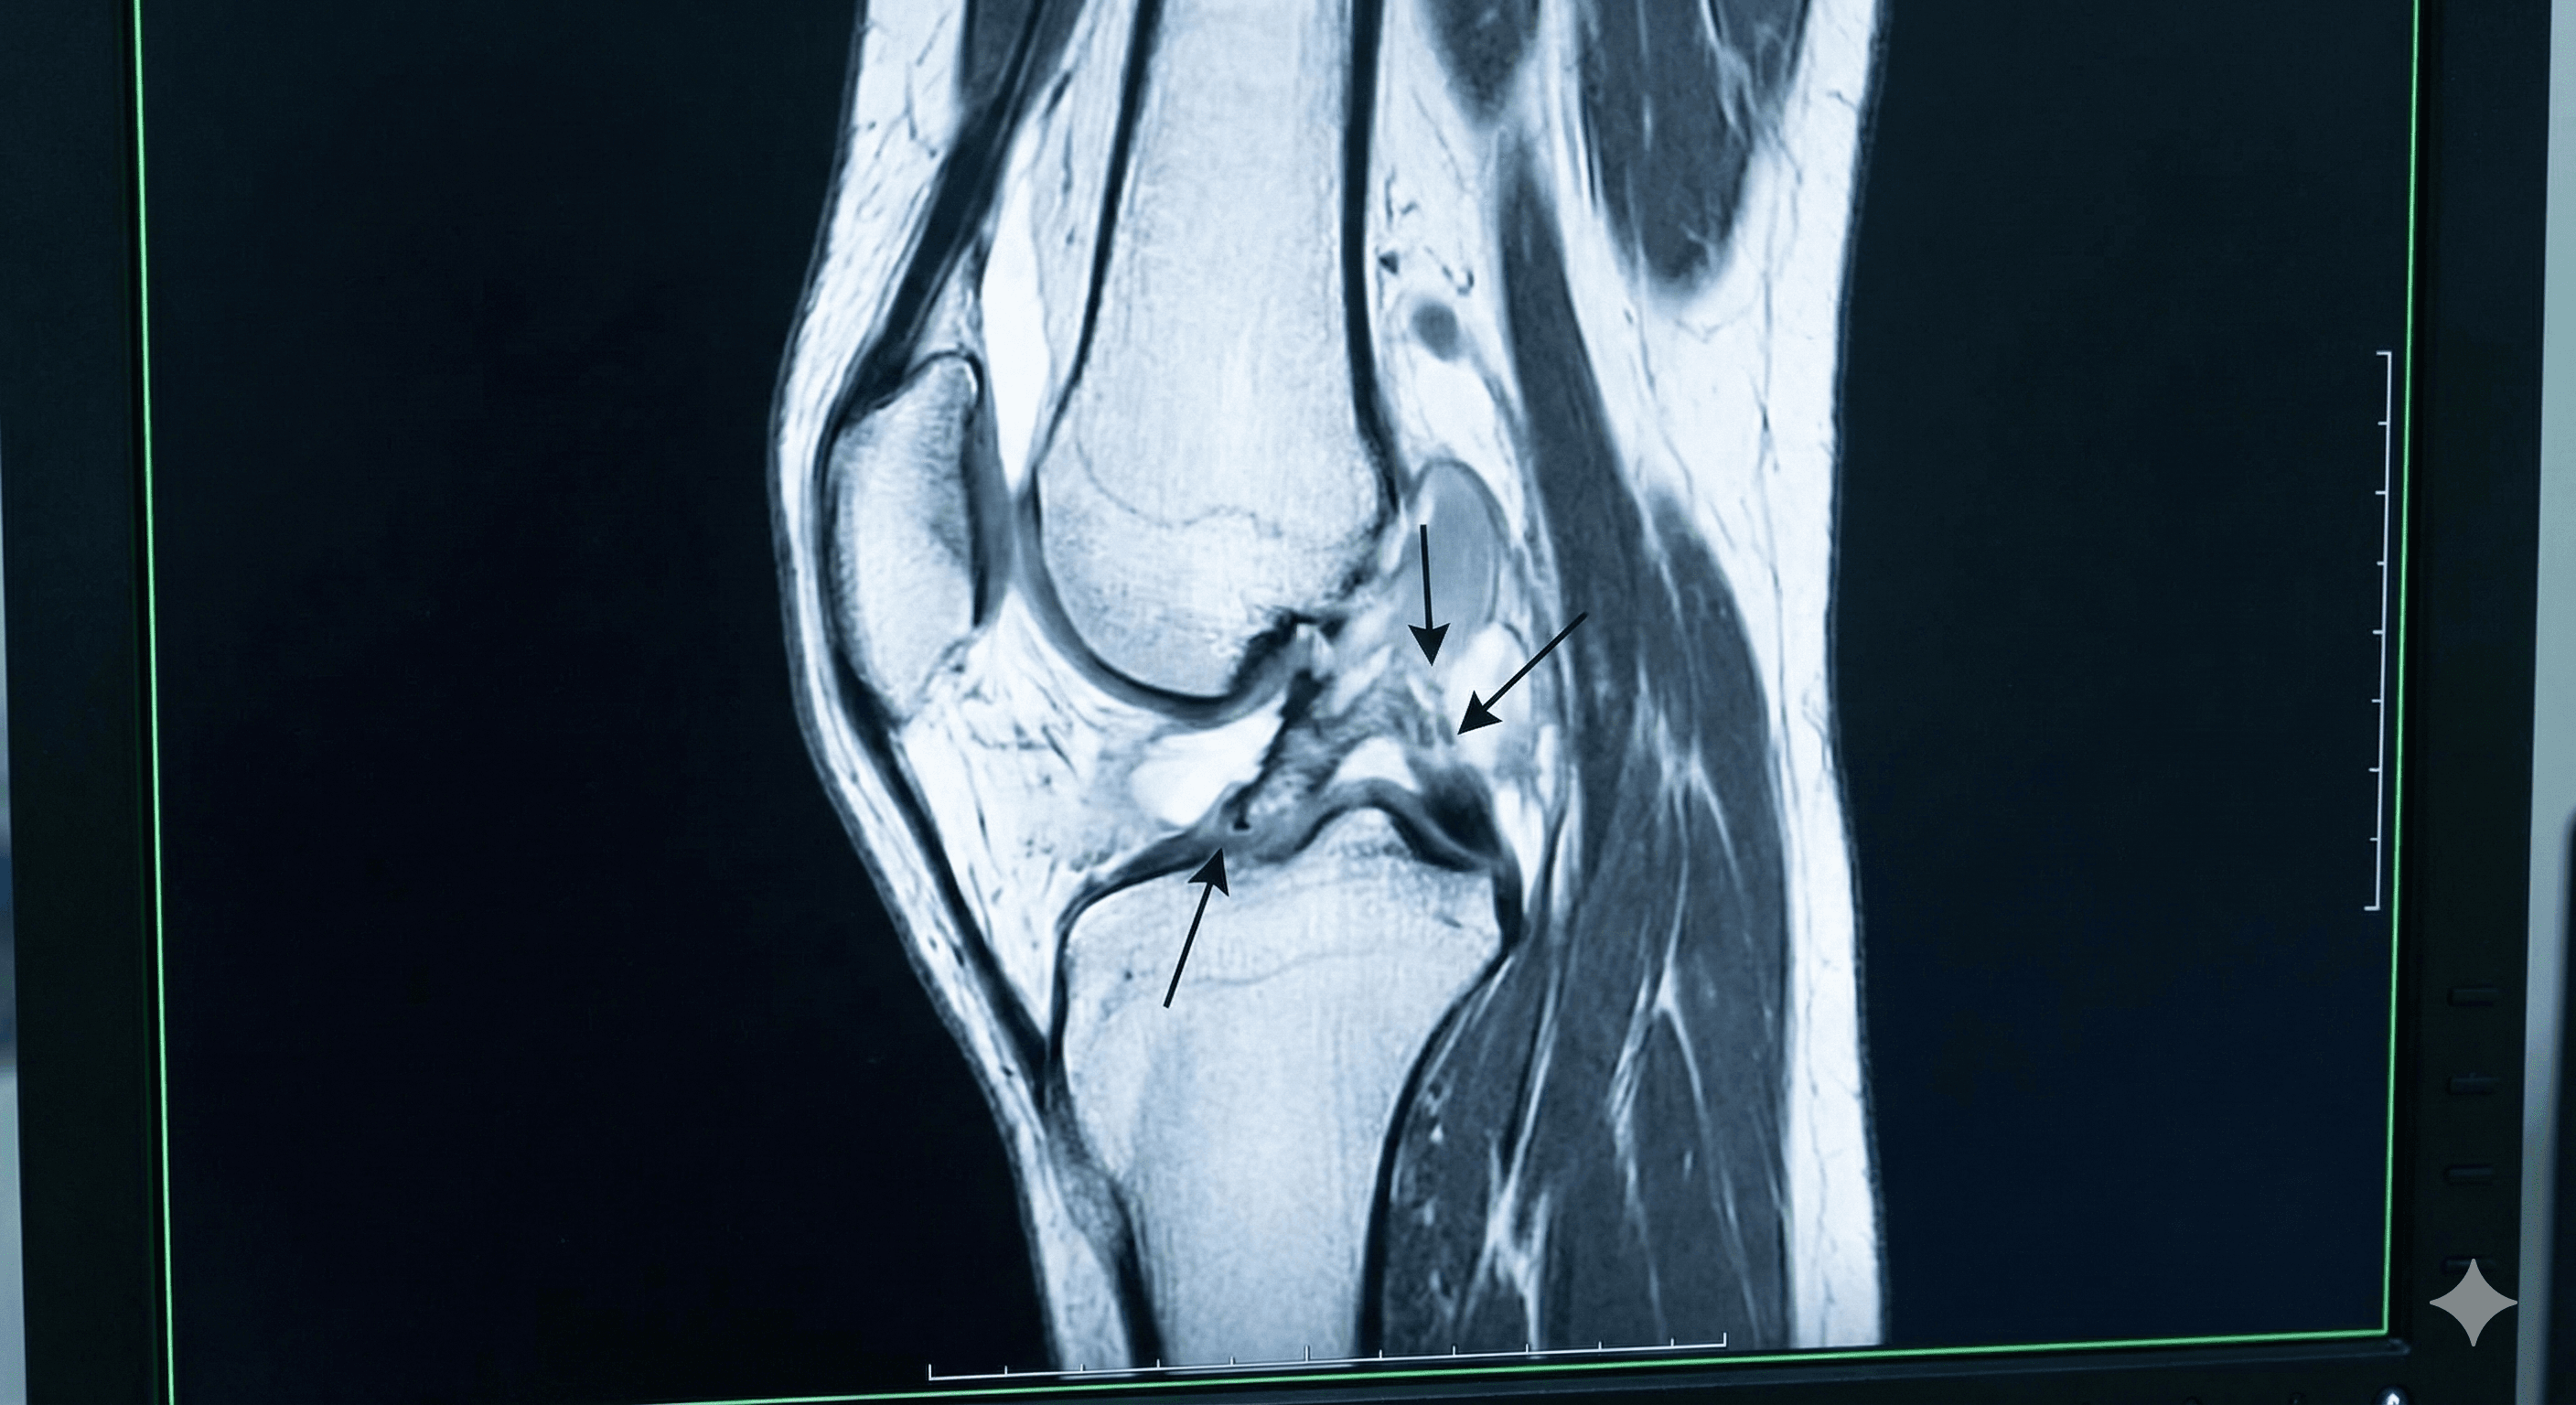

Desgarro del ligamento que estabiliza la rodilla, común en deportistas tras giros bruscos o caídas.

Cirugía para reconectar o reconstruir ligamentos y tendones dañados.